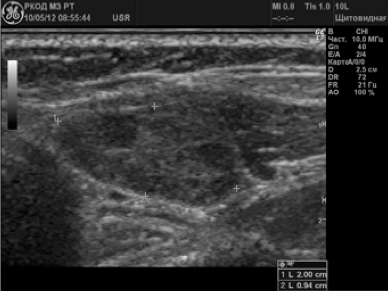

În 58 (38,2%) cazuri a fost suspectat ganglionilor limfatici metastatic. Alterarea LT avea dimensiuni de 6 până la 65 mm; 72,4% din nodulii limfatici au avut o formă sferică, P / PP<2,0; 10,3% — овальную, П/ПЗ>2,0; 17,3% - o formă neregulată sub formă de conglomerate. În 24 (41,4%) pacienți au fost identificați un singur ganglionilor limfatici schimbare; 34 (58,6%) - multiple. In 79,3% din ganglionii limfatici a fost nici o diferențiere în cortexul și poarta; 20,7% - poarta de acces determinat ca un mic incluziuni hiperecogene. 70,8% au fost ganglionii limfatici gipoehogennymi (Figura 3). 12% - anehogennoe; 17,2% - structura neomogena cu porțiuni ridicate și ecogenicitate coborâte clorhidric cu incluziuni lichide și calcifieri (Figura 4.).

Metastataz structură solidă-lichidă nodul limfatic la nivelul gâtului

În 31% din cazuri, ganglionii limfatici aveau contururi aspre, neclare, care a fost privit ca un semn de infecție în țesutul turnante-ghidajelor. In modul Doppler color cer maparea în 17,2% din cazuri vizualizate-Rowan Vase penetrante dincolo de nodul limfatic in tesutul din jur, care a fost considerată ca o caracteristică suplimentară de infestare. În 10,3% din cazuri au avut invazie poruncile-dozrena în vase adiacente, deoarece nu a existat nici o graniță între peretele vascular și nodul limfatic. Atunci când se evaluează fluxul sanguin în afectat 75,9% DR a fost detectat de tip mixt.